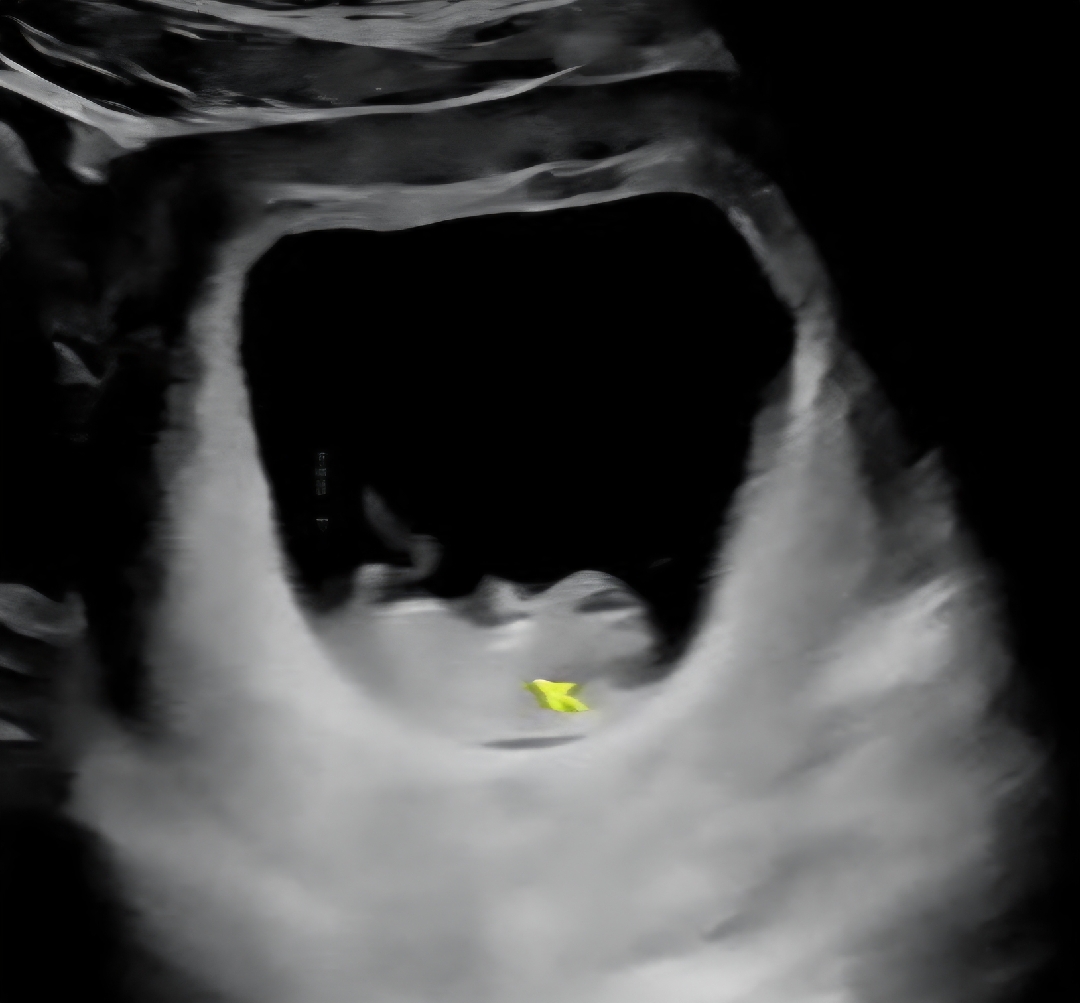

10주차 진입할 때 찍은건데 저처럼 아기집 크신분도 있으신가요 ㅇㅅㅇ?? 아기크기는 주차수에 맞게 잘 크고있고 심장소리도 좋다구 했어요 저처럼 아기집 큰 분 계신가요 ?? 빌리에서는 못 본것 같아서요.. 다른 문제가 있는 건 아니겟죠... 아기집이 크면 배도 빨리 나오는지 궁금 하기도햐고..궁금한게 많네요! 폭풍서칭 하니까 아기집은 아기가 짓는거라 던데 방도딥땨 크게 지어놧네혀..ㅎㅎ 고슈님들 참견해주세용

저도 이정도에요! 이게 딱 9주 2일차 였어요 ㅎㅎ

대부분 그정도 하지 않나요?초음파 보는 각도에 따라 크기는 달리보일수도있어용 아기집 큰거보다는 작은게 문제라 봤던거 같아요ㅎㅎ 저는 8주차에 이정도 였네요! 걱정마세용